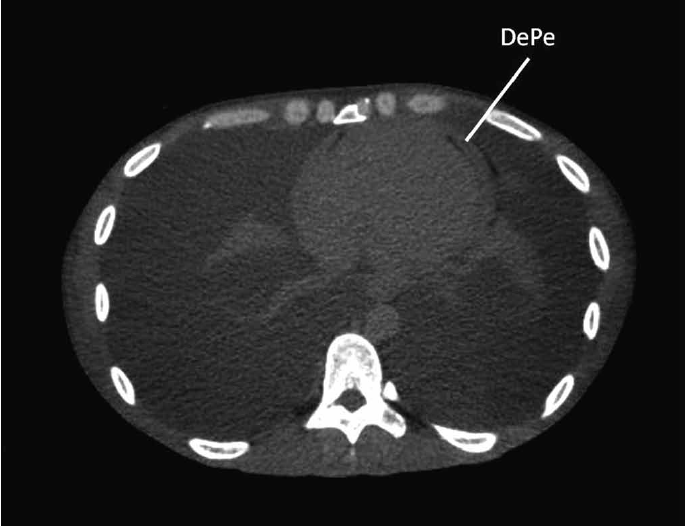

El ecocardiograma reveló insuficiencia mitral grave y pericardio engrosado con reducción del deslizamiento entre sus hojas, con variación respiratoria superior al 25% del flujo mitral, lo que indicó restricción. La tomografía computada mostró derrame pericárdico (Figura 2). A pesar del PPD negativo, la principal sospecha diagnóstica fue una PC causada por TB y, de esta forma, se inició un esquema con rifampicina, isoniazida, pirazinamida y etambutol (RIPE). Este esquema fue suspendido al séptimo día debido a la aparición de ictericia. La búsqueda de BAAR (bacilos acidorresistentes) y el cultivo para el BK en el líquido pleural fueron negativos. Se discutió la posibilidad de la realización de una pericardiectomía, debido al patrón restrictivo, pero no fue realizada, pues hubo un empeoramiento importante del cuadro clínico, con el agravamiento del derrame pleural bilateral según lo demostrado por la resonancia magnética nuclear (Figura 3). Se decidió entonces por el reinicio escalonado del esquema RIPE y mantenimiento de la terapia con corticoides. El paciente no presentó efectos adversos y evolucionó con una mejora progresiva del cuadro clínico. Los signos de restricción desaparecieron en los exámenes ecocardiográficos seriados después de la introducción del esquema RIPE y corticoterapia. Recibió alta hospitalaria después de cuatro meses de internación.

Figura 2. Tomografia computada de tórax mostrando el derrame pericárdico (DePe).